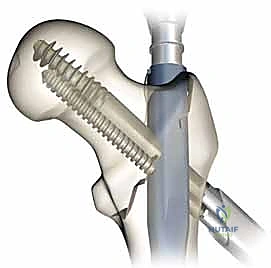

التسمير النخاعي الرأسي الفخذي هو تقنية جراحية متطورة تعتمد على مبدأ "تقاسم الحمل الميكانيكي" (Load-Sharing Device). بدلاً من تثبيت شرائح ومسامير على السطح الخارجي للعظم (والتي قد تنكسر تحت ضغط الوزن)، يتم إدخال سيخ أو مسمار طويل وقوي مصنوع من سبائك التيتانيوم الخالص داخل التجويف النخاعي (المركزي) لعظمة الفخذ.

يتكون هذا النظام الجراحي من:

1. المسمار النخاعي الرئيسي (Intramedullary Nail): مسمار طويل يمتد داخل القناة النخاعية لعظمة الفخذ.

2. المسمار الرأسي/العنقي (Cephalic/Lag Screw): مسمار سميك وقوي يمر من خلال الجزء العلوي للمسمار النخاعي، ويدخل في عنق ورأس عظمة الفخذ لتثبيت الكسر الرئيسي.

3. مسامير الغلق السفلية (Distal Locking Screws): مسامير صغيرة تُثبت أسفل المسمار النخاعي لمنعه من الدوران أو الانزلاق داخل العظم.

هذا التصميم العبقري يجعله أقوى نظام تثبيت متوفر حالياً، حيث يمر محور تحمل الوزن عبر المسمار الموجود داخل العظم، مما يجعله مقاوماً للكسر والانحناء، ويسمح للمريض بالاعتماد على ساقه في وقت قياسي.